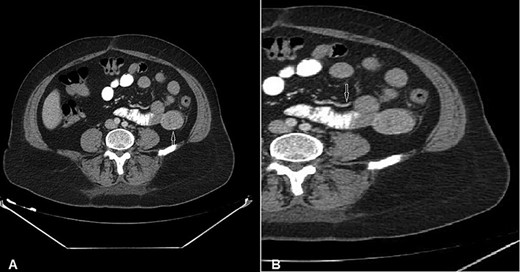

A 54-year-old woman presented with a history of multiple episodes of melaena and haematochezia accompanied by colicky abdominal pain and fatigue for the previous 3 days. Other than hypertension she did not have any other comorbidity. On primary physical examination she was pale and had a slight tachycardia but was normotensive. Abdominal examination was unremarkable. Digital rectal examination confirmed melaena stool mixed with fresh blood. Laboratory tests revealed a low haemoglobin of 7.2 g/dl. Clotting tests were normal. The patient was commenced on IV fluids and a transfusion with packed red blood cells. Emergency gastroscopy to the third part of the duodenum did not show any evidence of active bleeding. She continued to pass large amounts of melaena and fresh blood and her haemoglobin was noted to have dropped to 5.4 g/dl. A colonoscopy was decided against. She received further packed red blood cells and underwent an urgent computed tomography (CT) scan with oral and IV contrast. This showed a well-defined homogenous extraluminal mass (4 × 3.5 cm) in the proximal jejunum with mesenteric neovascularisation. There was no evidence of intra-abdominal metastases or enlarged lymph nodes (Figs 1 and 2). These findings were most suggestive of a bleeding GIST. Angiography and embolisation facilities were not available in our institution. The patient was becoming unstable and so an urgent laparotomy was required.

CT of the abdomen with Intravenous and oral contrast (axial section) shows: (A) 4 × 3.5 cm well-defined homogeneous extraluminal mass of proximal jejunum (white arrow) without intraperitonial metastasis or lymphadenomegaly; (B) mesenteric neovascularisation (white arrow).